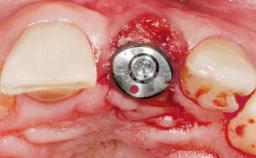

Immediate Placement of an Implant in a Maxillary Right Central Incisor Site

A 30-year-old female patient was referred to the office for the treatment of tooth 11. Her chief concern at the initial visit was to inquire, “Why is my tooth pink?” Upon clinical examination, it was determined that tooth 11 had a previous history of trauma and that the clinical crown had become noticeably pink in color as a result of internal resorption. This diagnosis was confirmed radiographically, indicating a large radiolucency involving the central and distal portions of the clinical crown. It was determined that restoration of this tooth was not possible, and that extraction was indicated. The presence of a mid-line diastema, which the patient wanted to reproduce, directed the treatment plan for tooth replacement utilizing a dental implant.

Type of Implants One-Piece|Reduced-Diameter

Placement Protocol Immediate implant placement

Tooth Site Maxillary incisor or canine

Socket Morphology Single-root socket

Socket Integrity Sufficient, with intact bone walls

Bone Volume Sufficient, with intact walls